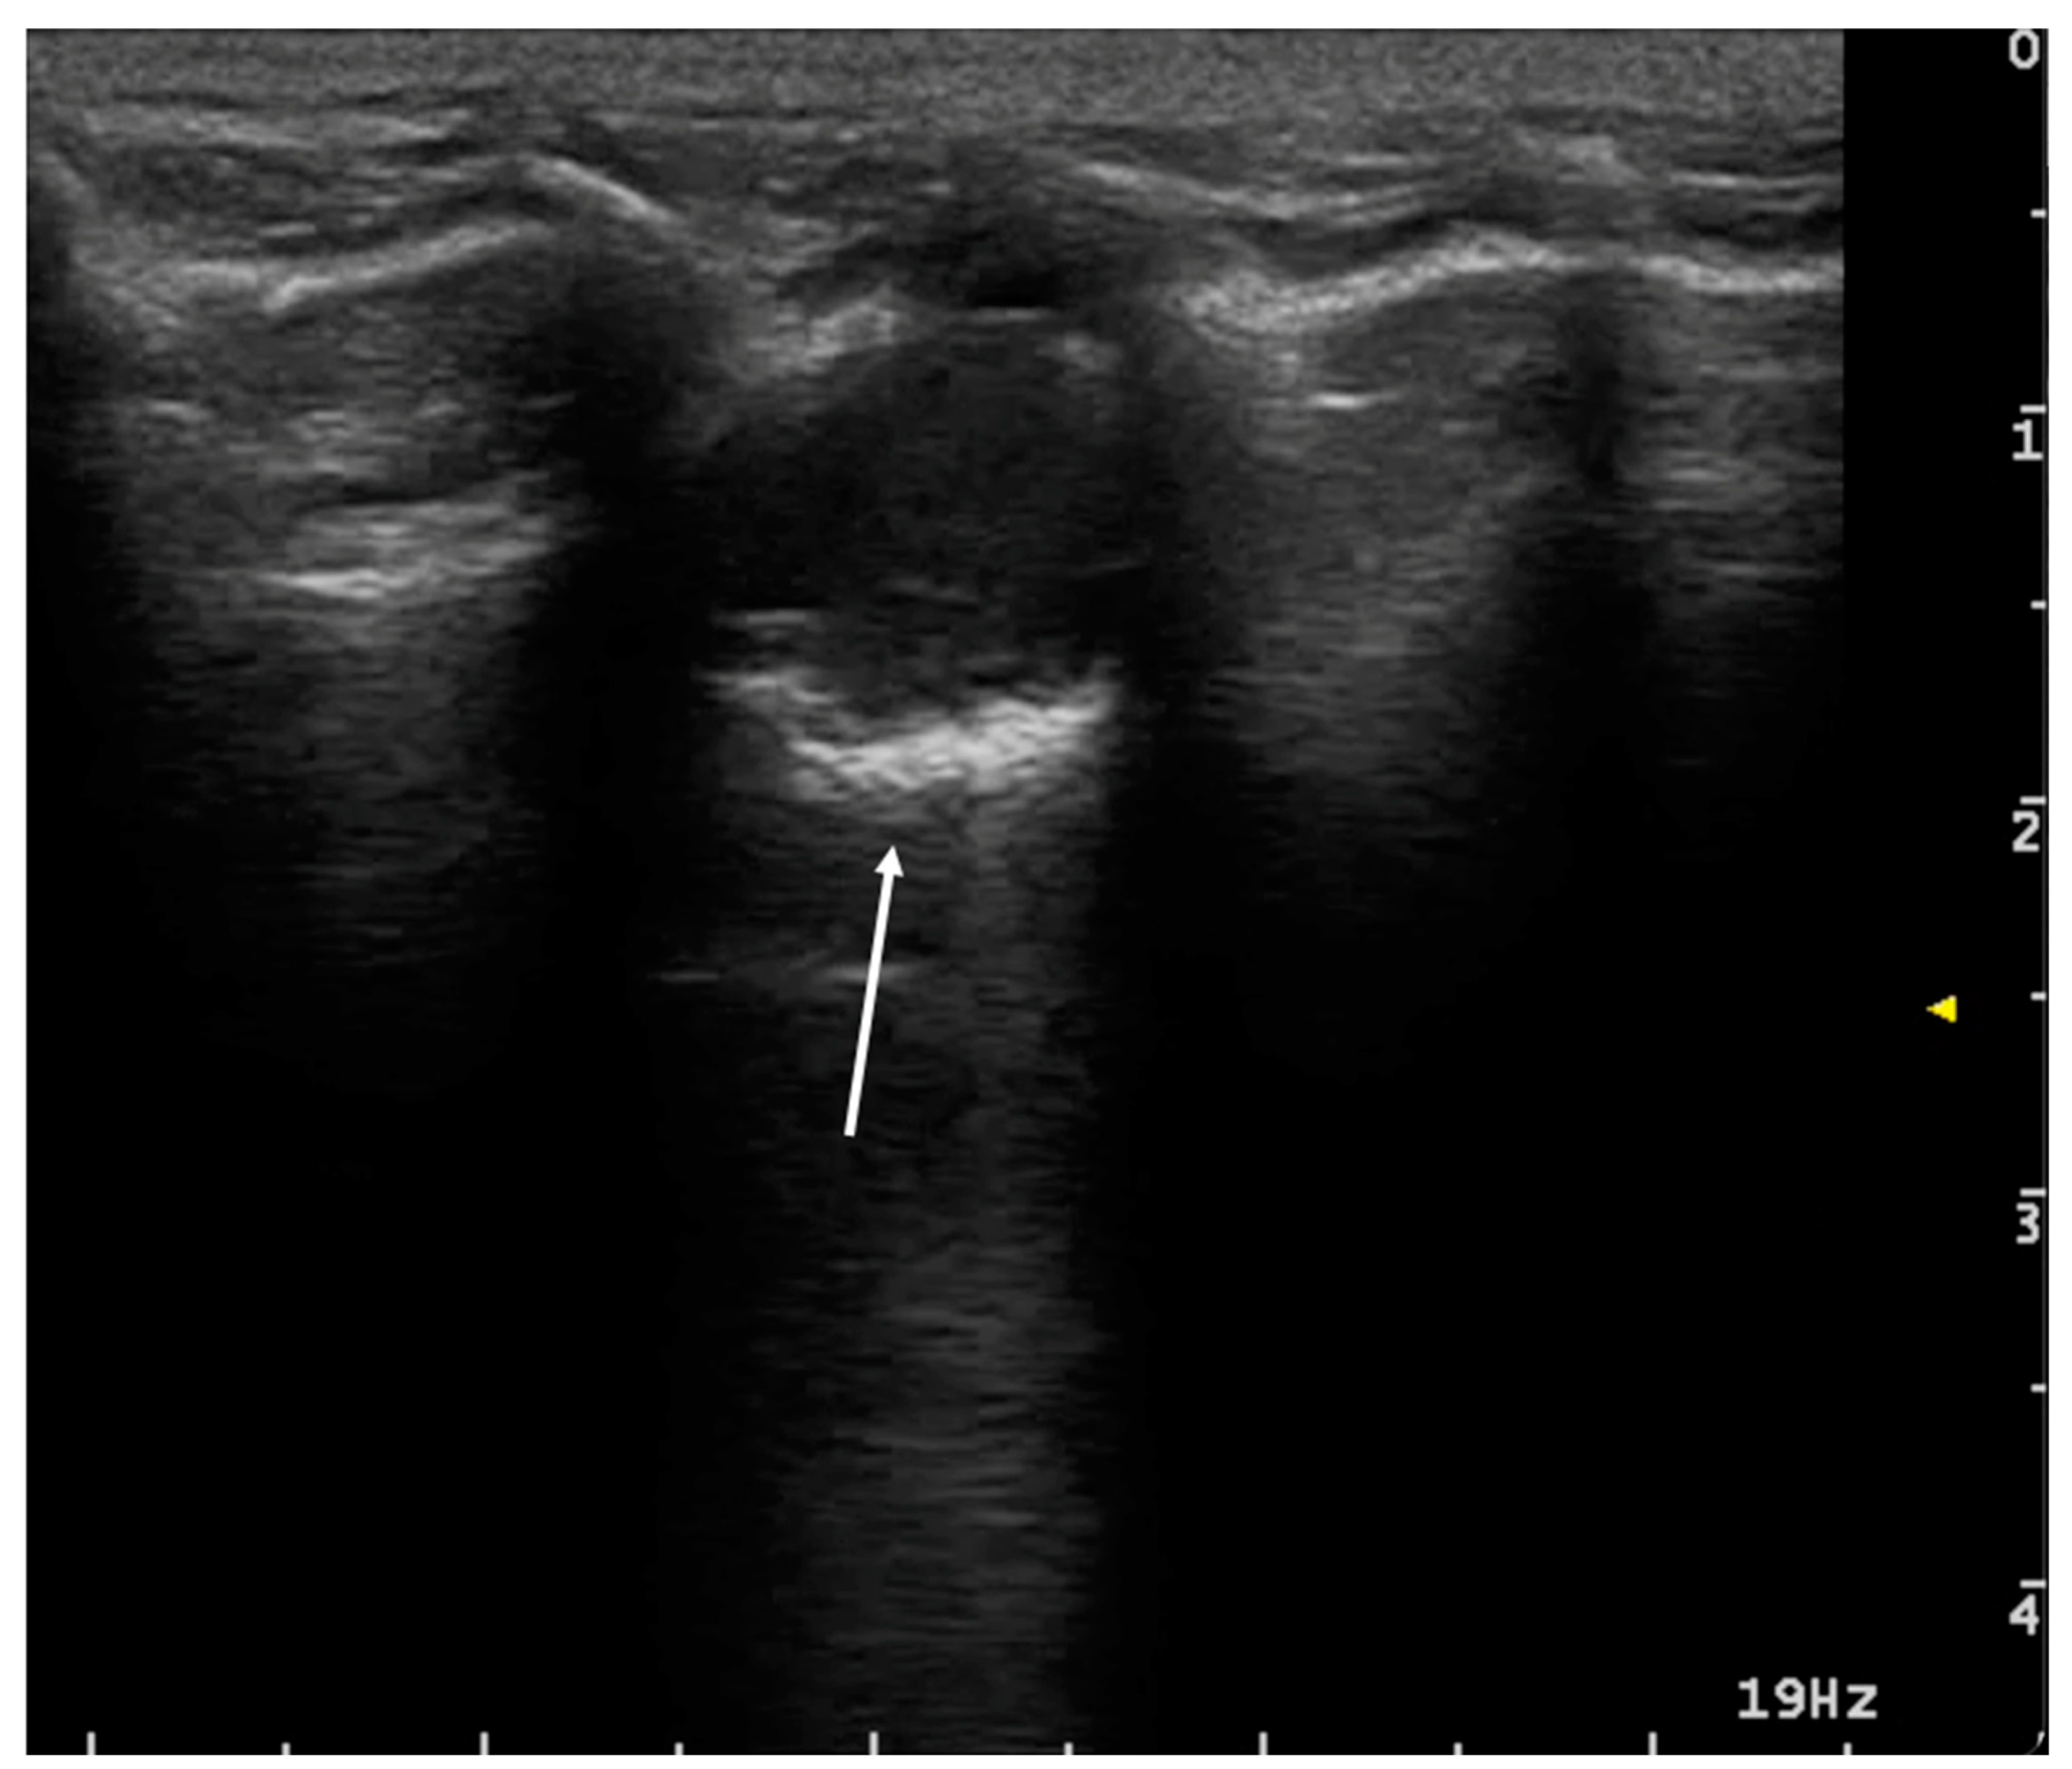

3.1.1. Pneumothorax